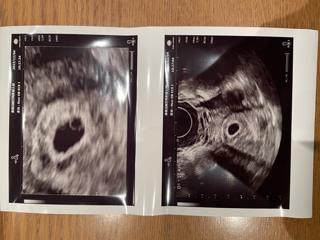

8ミリから19.8ミリまで成長していました。卵黄嚢も見えました。

来週には心拍確認できるかな?